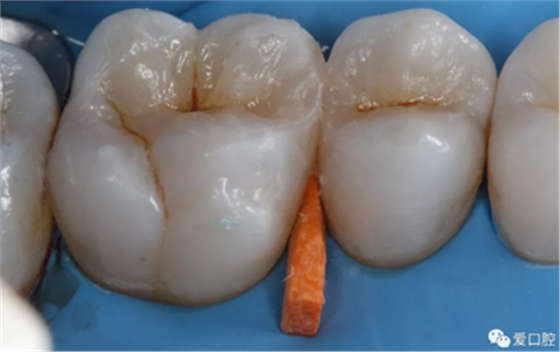

六、 充填體折斷或脫落

腐質(zhì)去除不干凈,充填體與牙本質(zhì)、牙釉質(zhì)未形成有效粘接。粘接時(shí)隔濕不良,血液或唾液污染創(chuàng)面,造成粘接失敗。窩洞設(shè)計(jì)缺陷。如 PPT20 圖示在直接承力的位置,較薄的充填體的邊緣容易受力發(fā)生折斷。 凹形斜面保證了充填體的邊緣厚度從而增加了抗力 。